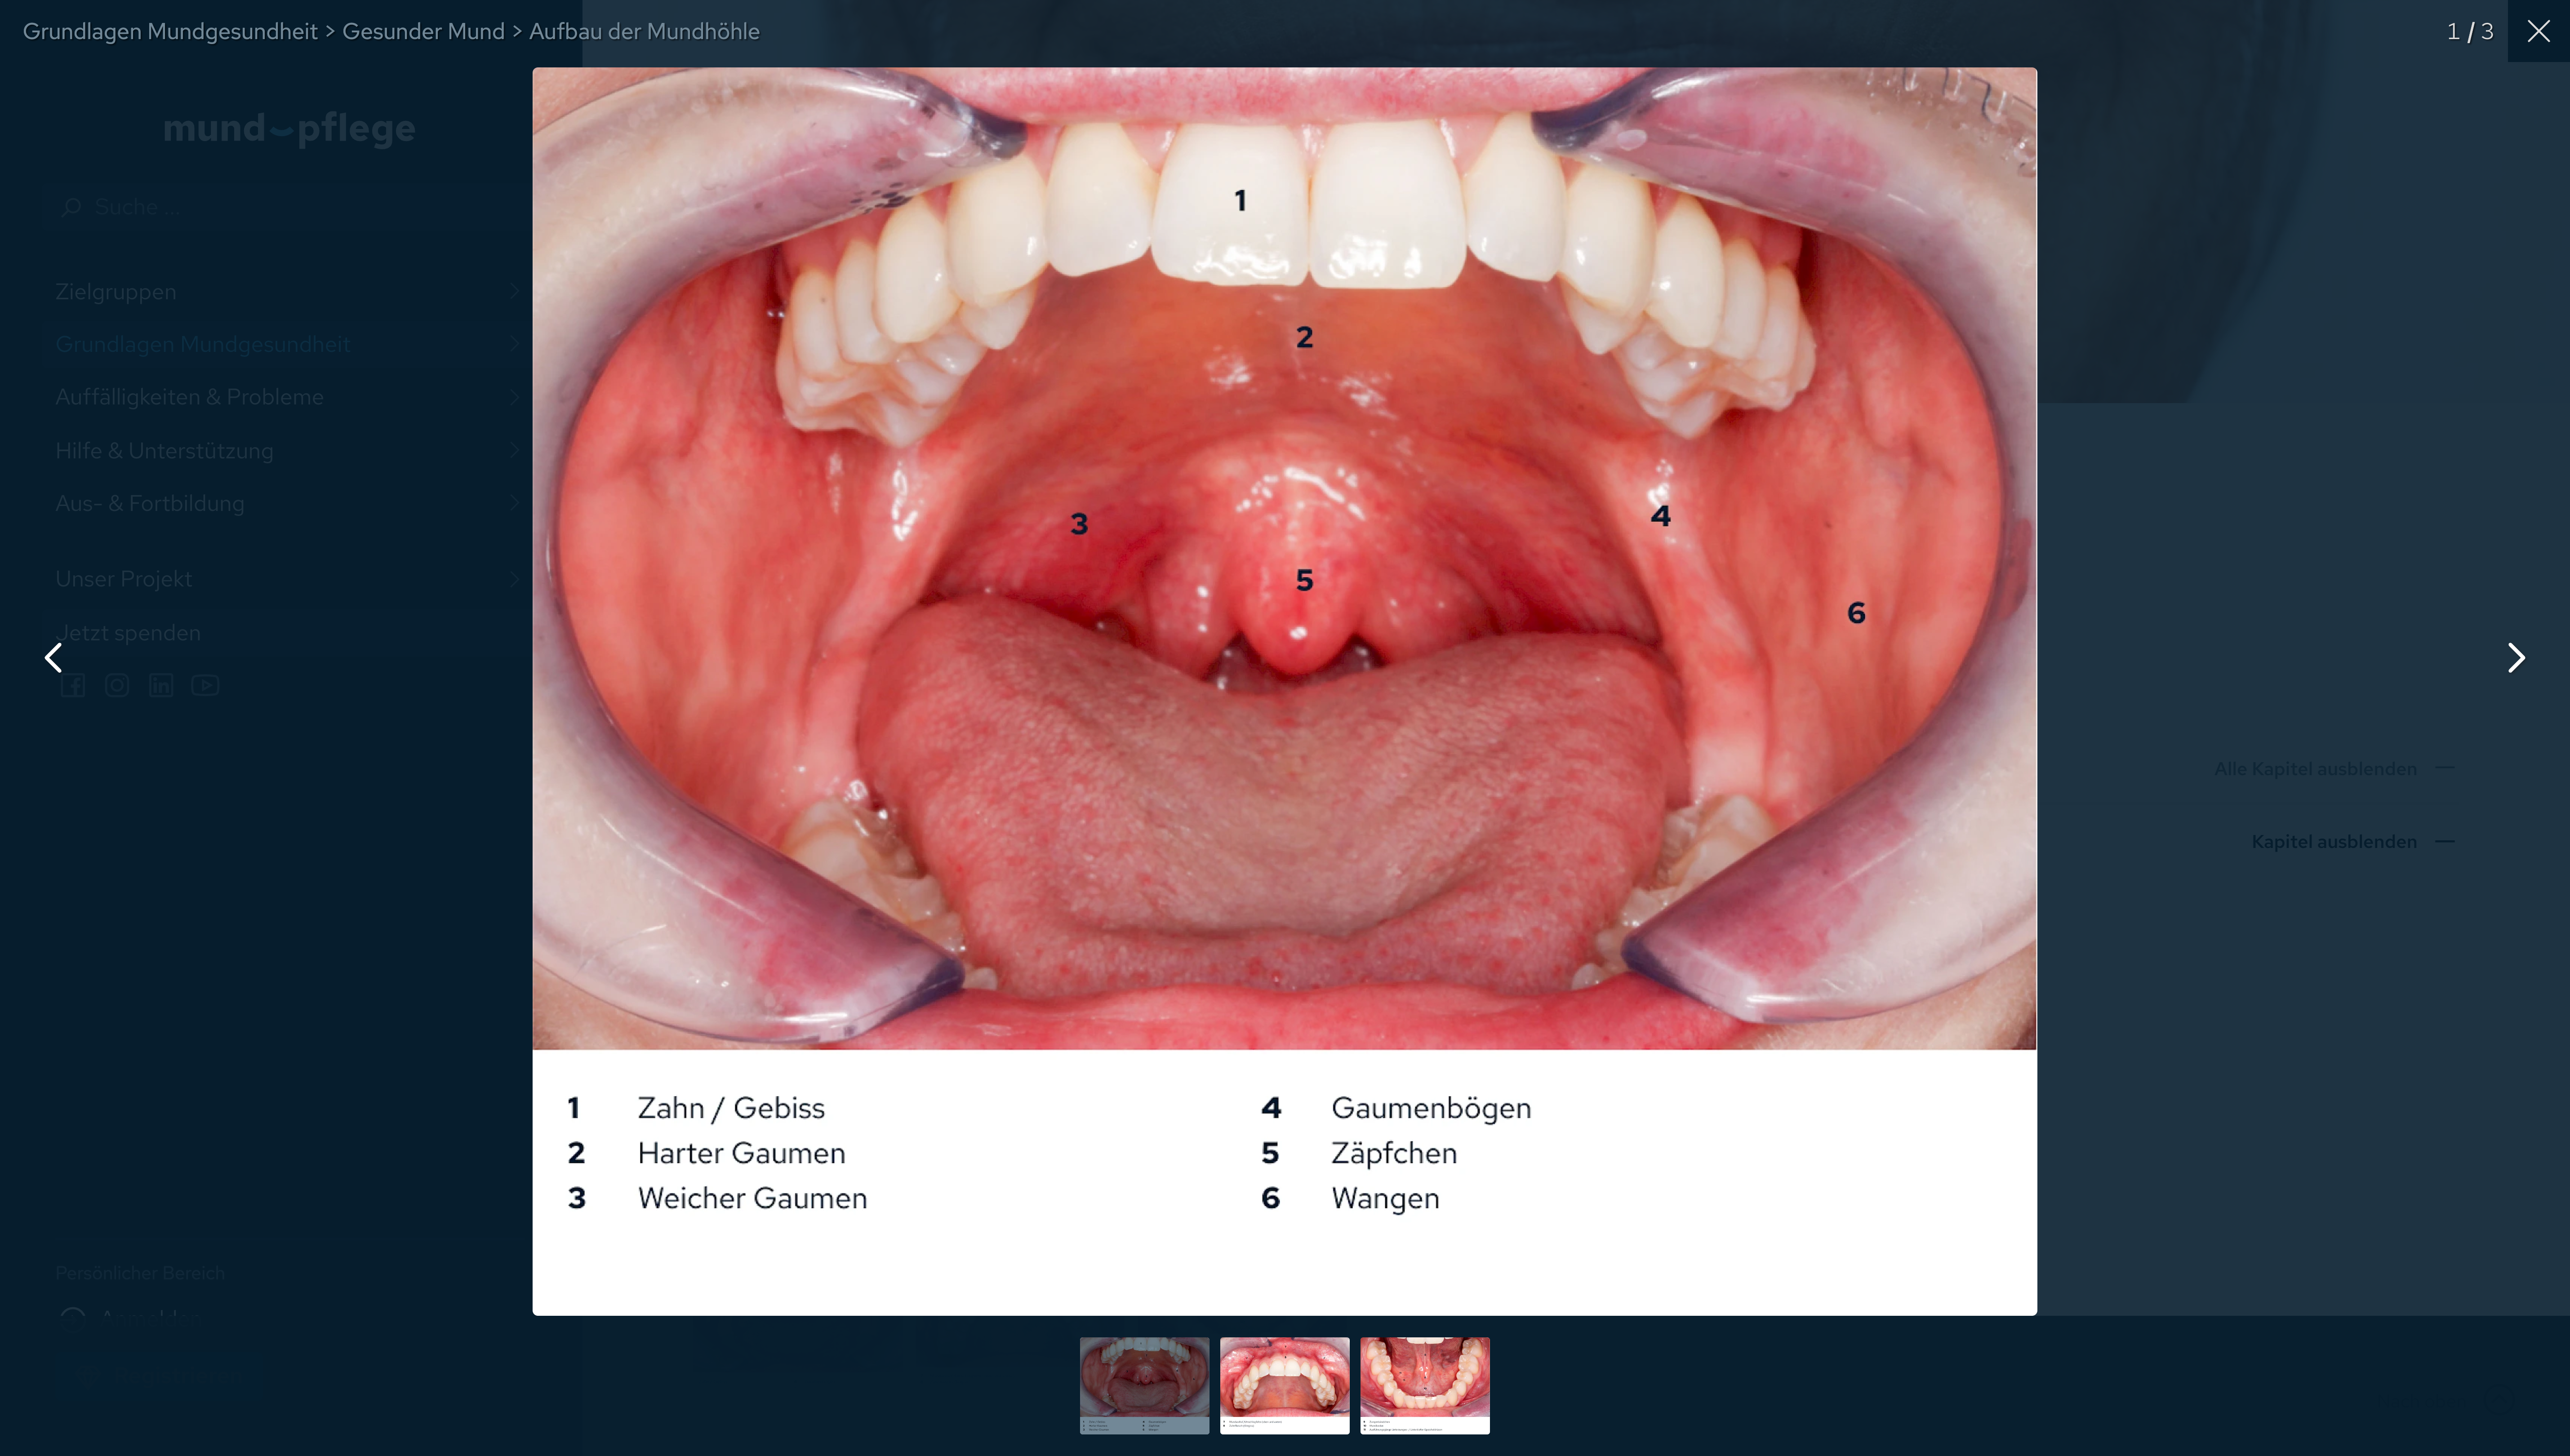

Gesunder Mund: Galerie (.png) 8,9 MB